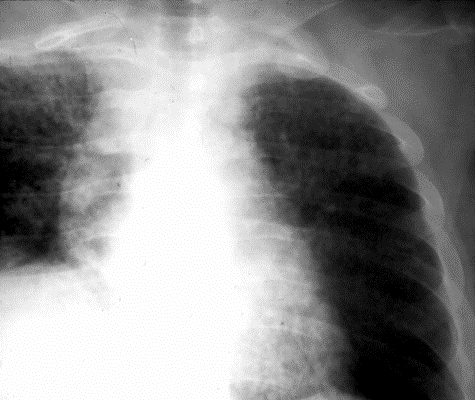

A PA of the chest shows a right hilar mass lesion and a miliary infiltrate. A modified acid fast stain of an aspirate from one of the skin lesions is shown below (see panels 2 & 3 below).

Nocardia asteroides is an opportunistic aerobic bacterium of higher order whose physical characteristics resemble those of actinomyces - a strictly anaerobic organism. Both species are Gram positive branching beaded coccobacilli, whereas nocardia is also modified acid fast positive (see right panel above). There are over a hundred nocardia species, many of which are implicated in human disease. Nocardia is a ubiquitous soil organism involved in the decay of organic materials.Nocardia usually gains entry through the lungs where it is characterized by its ability to cause a subacute pneumonia and to mimic miliary and cavitary tuberculosis and tumor (see middle panel above). In the host, with defective cell-mediated immunity, dissemination to the brain (most common), skin (see left panel above), and internal organs, may occur. In addition to his skin and pulmonary involvement, the presented case had nocardia endocarditis and a one liter abdominal wall nocardia abscess. Trimethoprim (10-20 mg/kg)-sulfamethoxazole (50-100 mg/kg) (TMZ-SMX) given in two divided doses per day is the drug of choice in most cases of nocardia infection. Daily doses TMZ-SMX doses can be reduced to as little as 5/25 mg/kg after induction therapy. For immunocompromised hosts and for those who are immunologicaly competent with brain abscesses, treatment should continue for 12 months. Pulmonary involvement in normal hosts requires 6-12 months of treatment. Unfortunately, the presented case expired despite the introduction of parenteral treatment with TMZ-SMX.